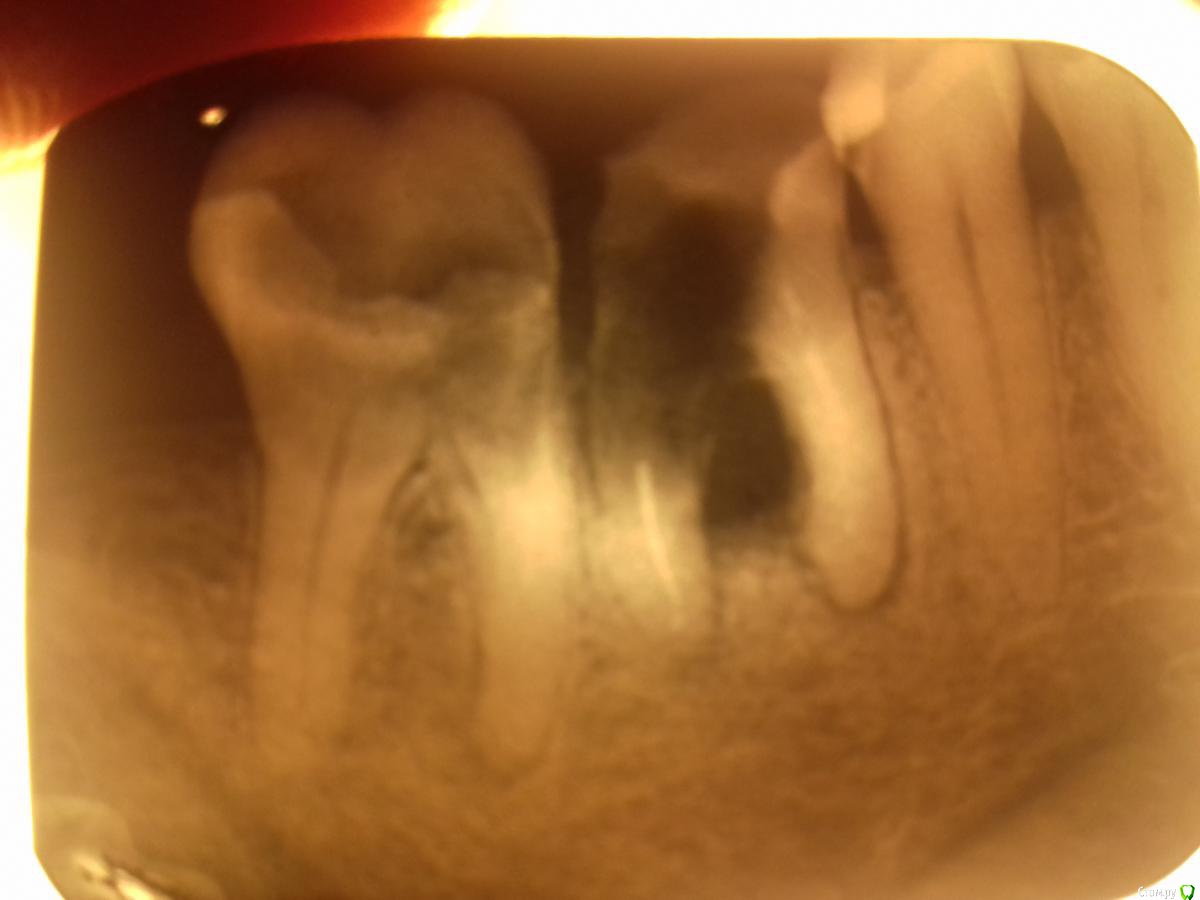

parallax Опубликовано 19 августа, 2017 Поделиться Опубликовано 19 августа, 2017 Это тот 47, что на снимке? Там кариес ниже уровня бифуркации. Удалять немедленно! Ссылка на комментарий

stomatpavel Опубликовано 19 августа, 2017 Автор Поделиться Опубликовано 19 августа, 2017 (изменено) Да, на снимке. Я тоже думаю что там не герметично... и уже несколько дней с 7 мучимся с пациентом...и сегодня уже жалобы на то что в ухо отдает :-( П.С. то значит никаких лайфхаков нету? Чтобы сохранить? Изменено 19 августа, 2017 пользователем stomatpavel Ссылка на комментарий

parallax Опубликовано 19 августа, 2017 Поделиться Опубликовано 19 августа, 2017 П.С. то значит никаких лайфхаков нету? Чтобы сохранить? Тут один лайфхак - сверкающие щипцы и элеваторы хирурга. 1 Ссылка на комментарий

Strider Опубликовано 20 августа, 2017 Поделиться Опубликовано 20 августа, 2017 По снимку - я б 47 удалил. Аккуратно зондом прозондируйте в области бифуркации под десной. Если проваливаетесь или ткани чувствуете что мягкие - удалять. Ссылка на комментарий

St. Опубликовано 20 августа, 2017 Поделиться Опубликовано 20 августа, 2017 Удалять оба 2 Ссылка на комментарий

Pan Опубликовано 20 августа, 2017 Поделиться Опубликовано 20 августа, 2017 согласен.,оба. Ссылка на комментарий